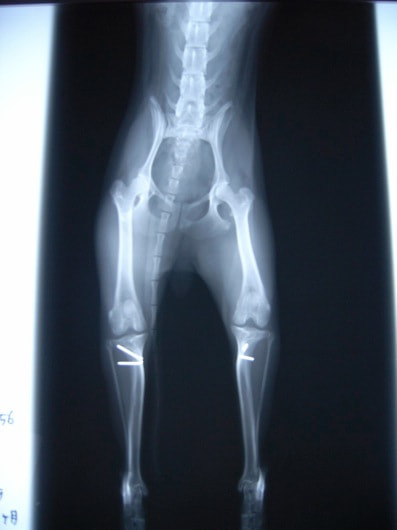

■ 症例22 ポメラニアン 1歳5か月 去勢雄

左後肢の挙上を主訴に来院した。整形学的検査、レントゲン検査より左右の膝蓋骨脱臼(左GradeⅡ〜Ⅲ、右Grade Ⅱ)を認めた。また、脛骨の前方引き出し試験の際に、引き出し兆候は認められないものの、疼痛が認められたため、前十字靭帯の損傷が疑われた。術中における、目視および関節内の操作によって、前十字靭帯の損傷や過伸展といった異常が認められなかったため、膝蓋骨脱臼の整復のみ実施した。手術手技は縫工筋及び内側広筋の解放、脛骨粗面の外側転位、滑車ブロック形造溝術、内外側関節包の縫縮を実施した。本症例は跛行もなく経過良好である。しかし、頸骨高平部の角度(TPA)が 右26.2°、左24.9°であり、解剖学的に前十字靭帯損傷のリスクが高いことから今後の経過に注意が必要である。